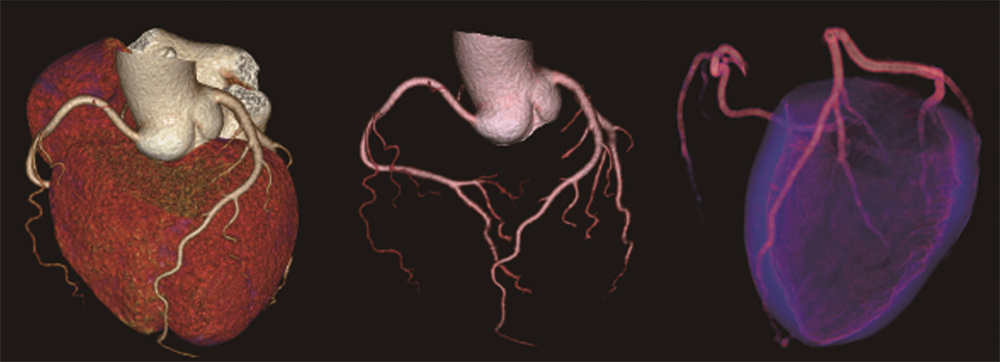

联影640层CT是中国CT届的“天花板”,集当今CT领域的顶尖科技于一身,将各项临床应用发挥到极致,为患者带来精准、舒适、安全的CT检查新体验。建立了心血管、神经、肿瘤、呼吸系统、泌尿系统及骨科专业等疾病的成像和低剂量筛查领域全新标准,真正实现全方位成像,结合AI人工智能技术,提高疾病诊断率。

凭借先进硬件平台和独有的AI冠脉追焦技术,不管是对于严重心律不齐、房颤、房扑,还是超高心率等一般CT做不了的心脏检查的情况,联影640层CT都可以获得高清的成像效果,助力精准临床诊断。

联影640层CT采用宽体采集,一次检查即可获得全脑平扫图像、动静脉造影图像和灌注图像,不仅可应用于急诊缺血性脑卒中的影像评估,还可助力脑血管畸形、脑动脉瘤等其他脑血管病的结构和功能评估。